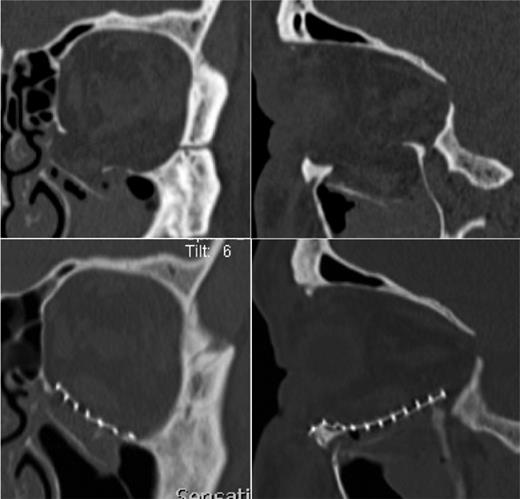

Computed tomography (CT 1 mm slices) presented a large, left-orbital floor fracture with caudal dislocation of the bone fragment and prolapse of the IR muscle and orbital fat into the maxillary sinus (Fig. 2a). Transection or disinsertion of the IR was not described.

The preoperative (a) and postoperative (b) CT of the left orbital floor fracture showing a satisfactory reposition of periorbital tissue and reconstruction of the orbital floor with a titanium-mesh.